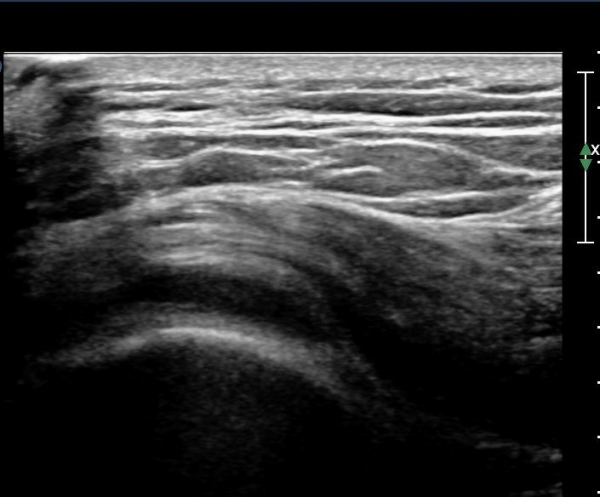

ŽÃËÀÚ¸¦ ¸Ó¸®ÂÊÀ¸·Î À̵¿ÇÏ´Ï ¼ö¾×Àú·ù°¡ ´õ ¸¹ÀÌ °üÂûµÈ´Ù(»çÁø 2, 3).